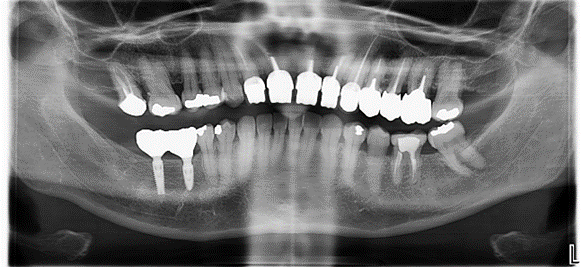

Les implants dentaires permettent aujourd’hui de remplacer les dents absentes de façon prédictible et peu invasive. De la reconstruction unitaire, plurale à complète, les implants donnent aux patients la possibilité de retrouver une mastication efficace et un sourire esthétique.

Pour assurer la pérennité du traitement implantaire, l’implant en titane doit être placer de manières à ce que la restauration prothétique assure la fonction occlusale. Il faut donc s’assurer dans les examens pré implantaire que l’os disponible correspond bien à de l’os utile.

L’autre impératif, est d’avoir évidemment suffisamment d’os en hauteur pour assurer l’ancrage, mais également en épaisseur afin que ce dernier qui si situe sur le pourtour du col implantaire soit vascularisé, et ainsi limité la résorption au cours du temps. Cet os périphérique protège également du risque de rupture du col de l’implant, car c’est la zone de jonction avec l’élément prothétique.